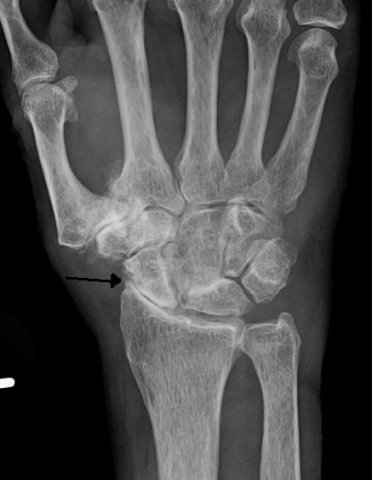

Reumatoidalne zapalenie stawów jest najczęściej występującym procesem zapalnym stawów, który początkowo atakuje ręce, kolana, stopy, a wraz z postępem również inne większe stawy. Choroba ta jest nieuleczalna, ale dzięki odpowiedniemu, kompleksowemu leczeniu można znacznie ograniczyć jej postęp. Terapia obejmuje leczenie farmakologiczne, fizykoterapię, rehabilitację, czasami akupunkturę, a przede wszystkim zmianę dotychczasowego stylu życia - więcej ruchu nieobciążającego stawów, zdrowa dieta, itp.